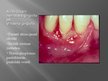

Mutes dobuma infekcijas